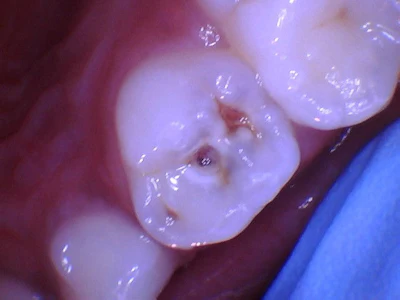

How would you manage this 4-year-old girl who had large caries on her upper first primary molar? (Figure 1).

Figure 1: Large caries on the upper first primary molar.Images and captions courtesy of Dr. Sanjukta Mohanta.

The ADA developed guidelines on how to manage moderate and large activated caries on primary and permanent teeth, with recommendations on caries removal and restorative materials. The guidelines recommend selective caries removal for moderate to large caries and composite resin as one of the materials that can be used for class I restorations. I follow these guidelines when managing my patients, so I did selective caries removal, which is leaving soft or firm (not hard dentin), and I restored her tooth with Luna 2 composite resin.